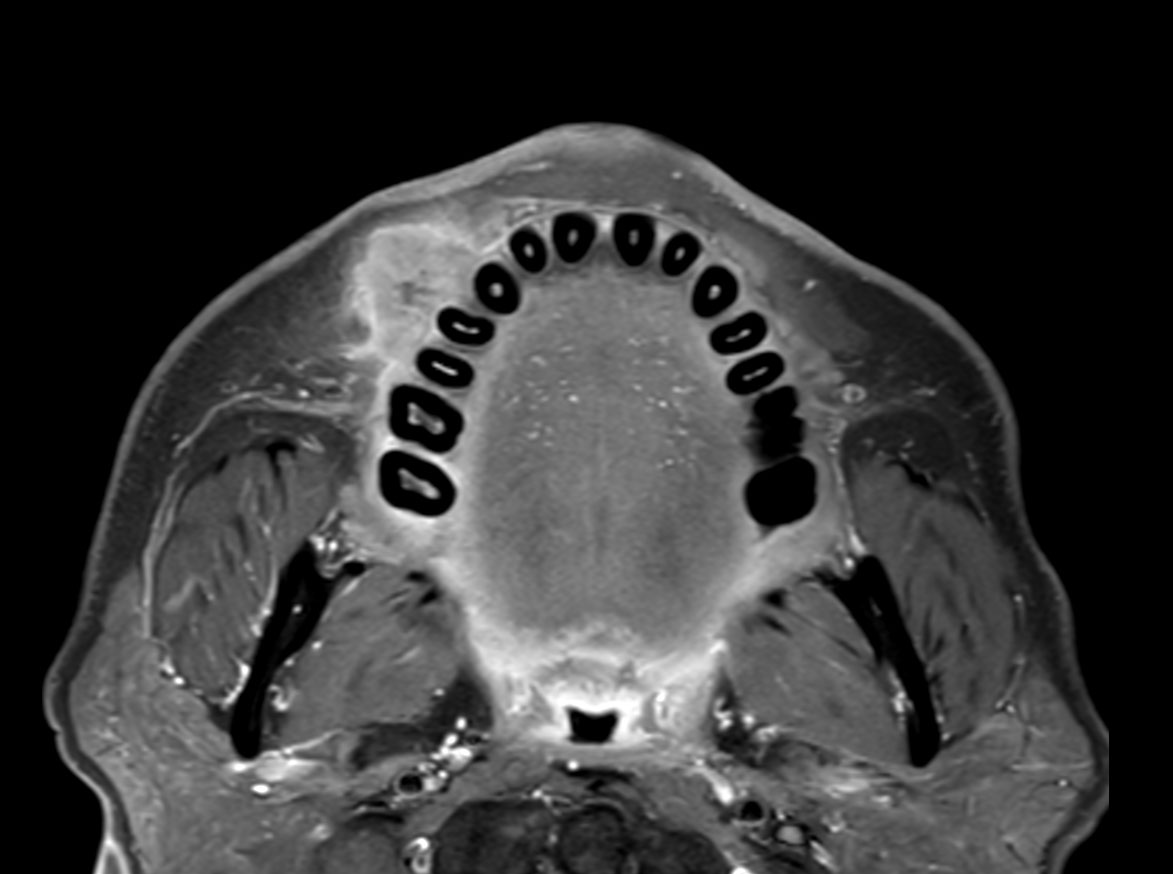

Axial T1w TSE

Axial STIR TSE